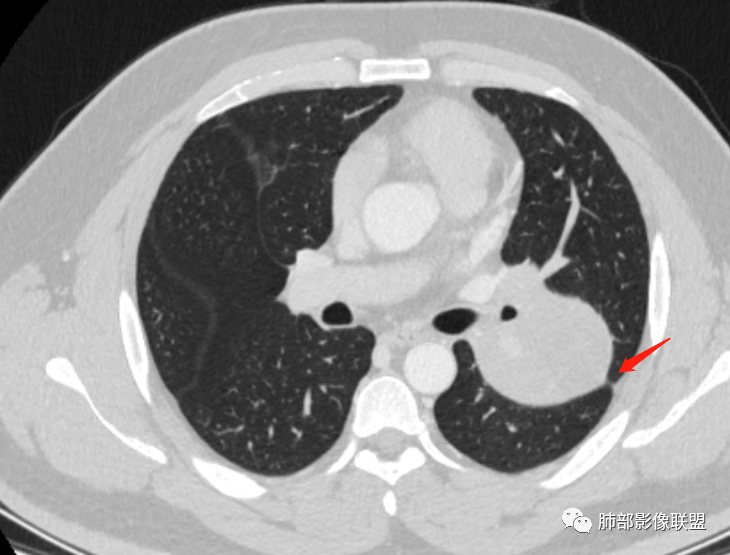

新月征很有特点,血管有特点

看血管像蛇纹状

蛇纹血管像sft,空气新月征像psp

青年男性,体检发现左肺不规则类圆形占位性病变,叶间裂区域,定位胸膜来源。左肺下叶支气管受压狭窄,但管壁光整,未见腔内阻塞或管壁受侵。包块边界清晰,浅分叶,内部密度不均匀,病灶后份见空气新月征。渐进性强化,增强动脉期见分支状血管,蛇纹血管征。肺门纵膈未见增大淋巴结,符合孤立性纤维瘤(SFT)。

5)肿瘤的强化程度及方式:增强扫描肿瘤早期实性成分呈不均匀斑片或斑驳样强化,亦可呈“ 地图样” 明显强化,强化程度不一,可呈轻度-显著强化;静脉期持续强化,多期增强及动态增强扫描均呈“快进慢出”型强化,且强化范围逐渐增大并趋均匀。肿瘤内部及周围常见多发粗细不等强化或流空肿瘤血管影。瘤体内“蛇纹血管”在其他诸如硬化性肺细胞瘤、错构瘤等等是非常罕见的。